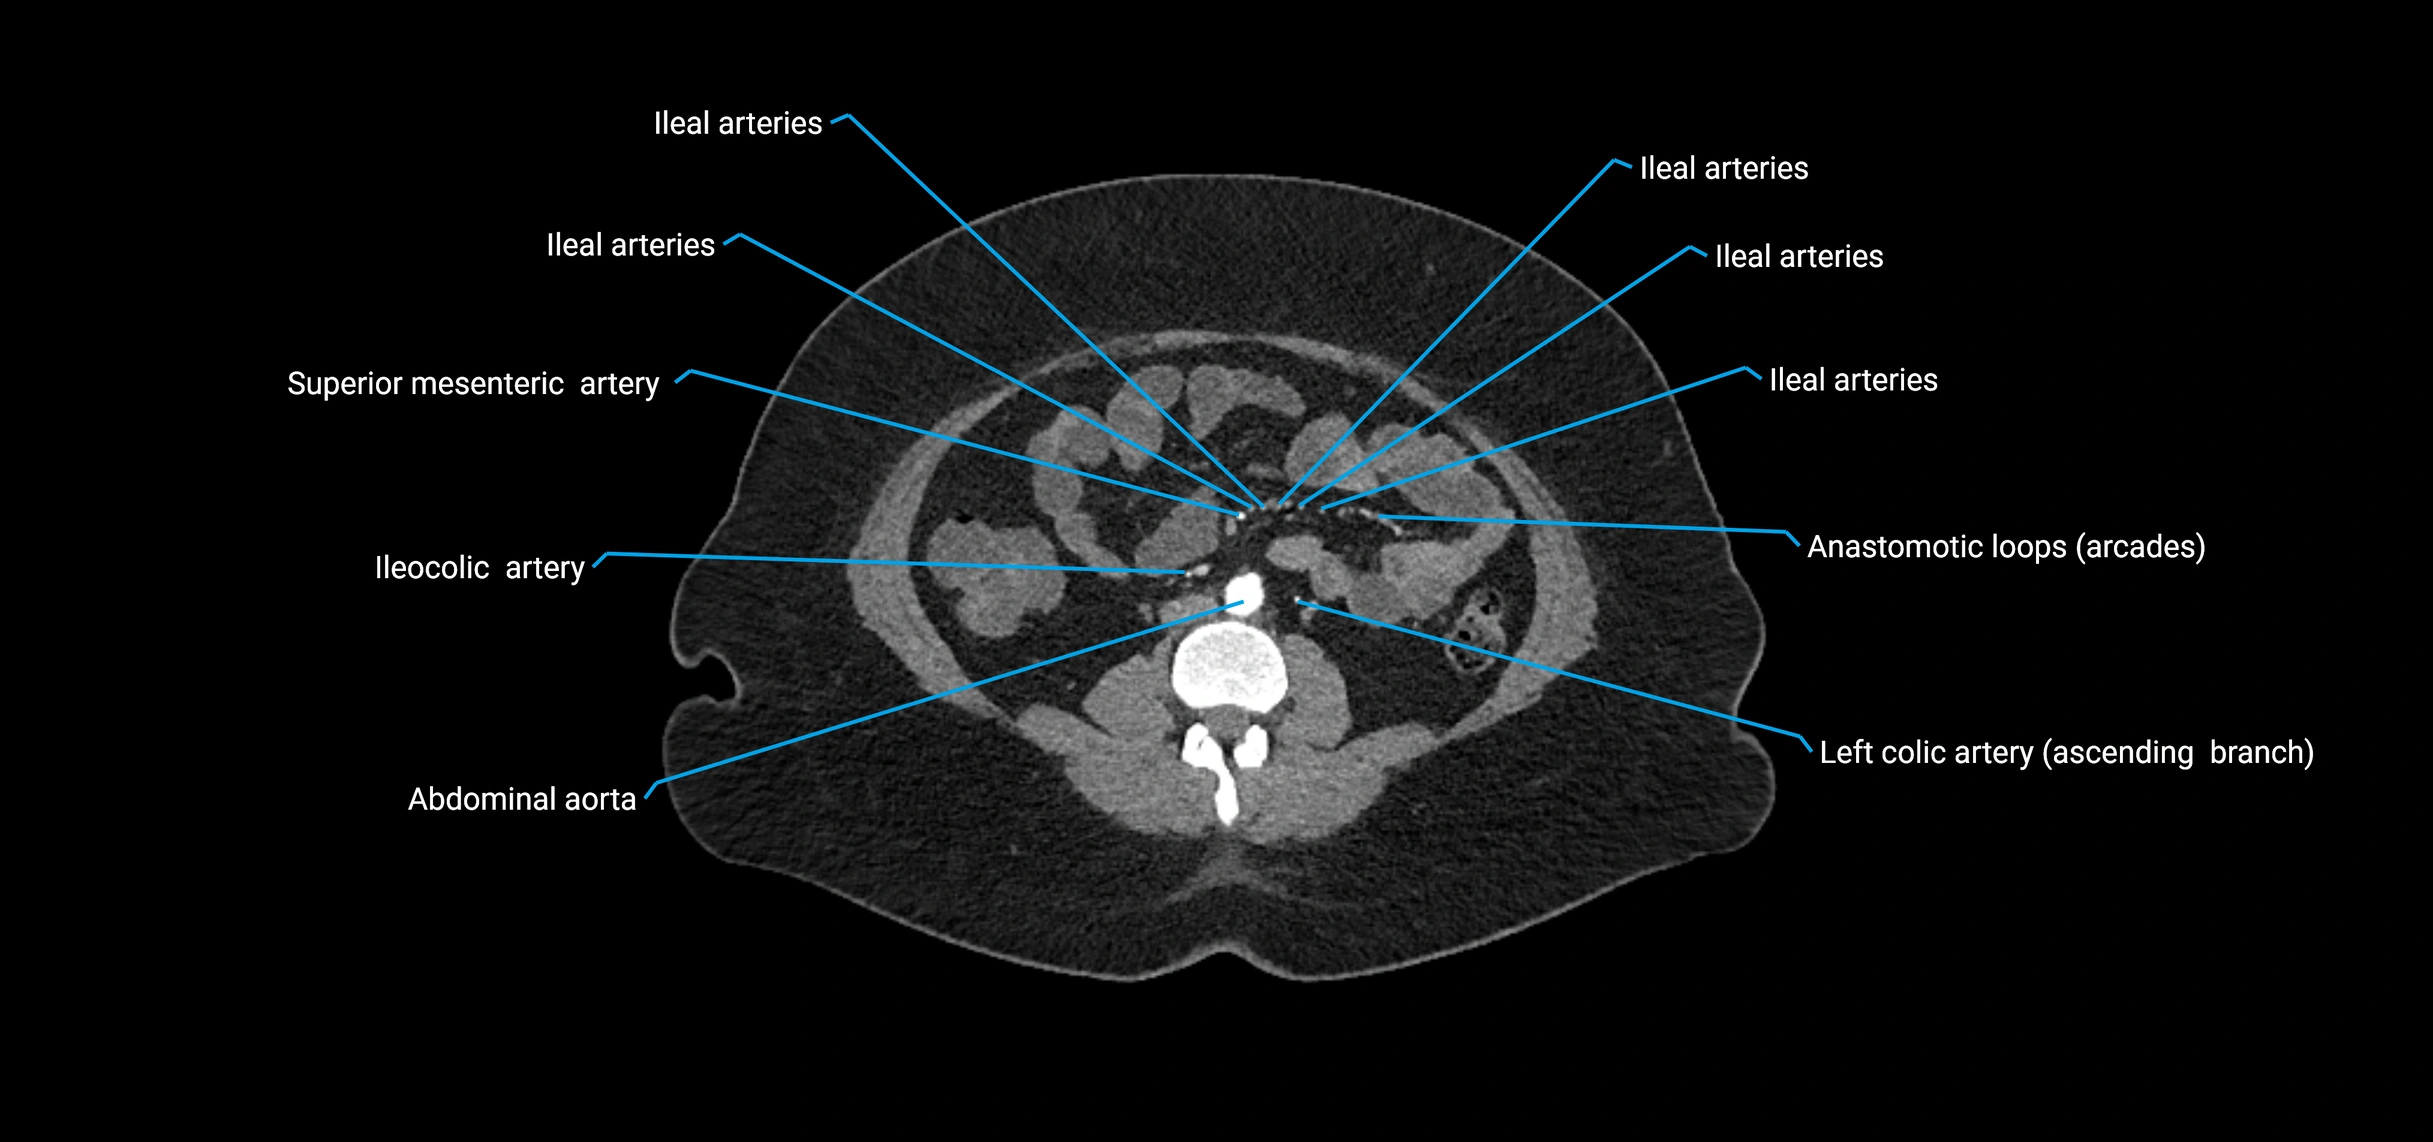

Contrast-enhanced CT (CTA):

• Gold standard for abdominal aortic imaging

• Provides excellent detail of lumen, wall, aneurysm, thrombus, and branch vessels

• Multiplanar and 3D reconstructions help in aneurysm measurement, stent graft planning, and dissection evaluation